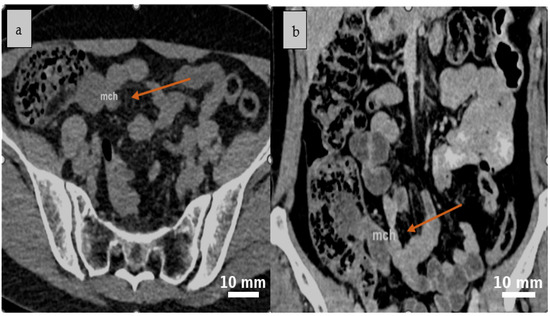

2.4. Diagnostic Assessment

3.2. Clinical and Imaging Features

3.2.3. Role and Limitations of Imaging